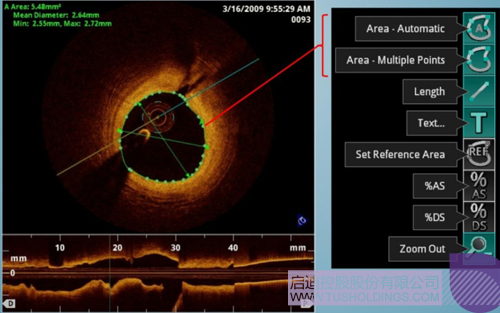

光學相干斷層成像技術(OCT)是一種新型影像技術,它利用弱相干光干涉儀的基本原理,檢測生物組織不同深度層面對入射弱相干光的背向反射或幾次散射信號,通過掃描,可得到生物組織二維或三維結構圖像。OCT由于具有極高的分辨率(10 um),可以對內膜性質和支架結構更加精確地辨別和分析。

在冠脈介入治療迅猛發展的今天,隨著復雜病變患者日益增多,血管內影像扮演了越來越重要的角色。OCT借助其高分辨率的圖像優勢,可以提供更清晰的病變特征和支架植入情況,OCT存在以下優勢:可更精確的檢測介入治療后的血管內情況,如夾層、支架貼壁不良、組織脫垂等,另外,它在管腔直徑和面積方面的測量精度更高。